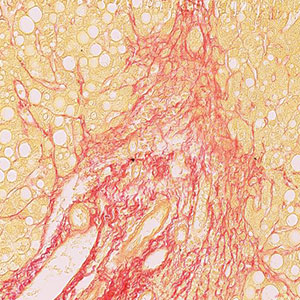

Sirius Red for collagen - kit

The kit supplies reagents of Sirius red stain to show collagen type I and III.